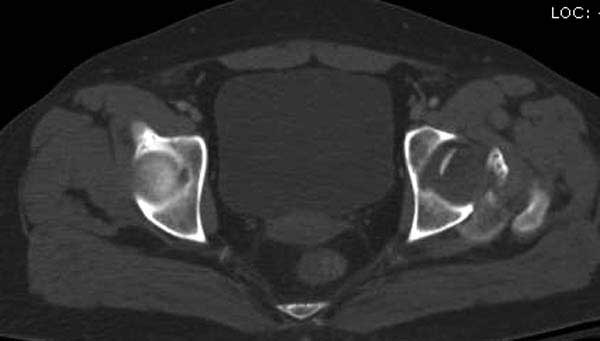

Женщина 28 лет, политравма.

По протоколу обследования больных с травмой сделаны все исследования и выставлен диагноз: разрыв печени и селезенки; множественные переломы ребер и лицевого черепа; стабильный перелом позвоночника, переломо-вывих головки левого бедра, перелом диафиза правого бедра, переломо-вывих правого тарана.

Имя     : 6 CT1.jpg

Тип     : image/jpg

Размер  : 26088 байтов

Описание: отсутствует

Url     : http://weborto.net:8080/pipermail/ortho/attachments/20120618/4c283bf6/attachment-0020.jpg